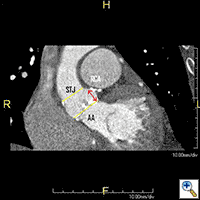

CT scan of the chest, abdomen and pelvis should be performed with three-dimensional reconstruction preferably with contrast if kidney function allows. The acquisition is performed with cardiac gating during the thoracic phase to assess the location of the coronary ostia in relation to the aortic annulus which is supposed to be > 10 mm to allow safe implantation of the valve (2). Additional assessment of the aorta CT scan and TEE are also important to delineate the morphology and measure the dimensions of the aortic root (Table, Figure 2).